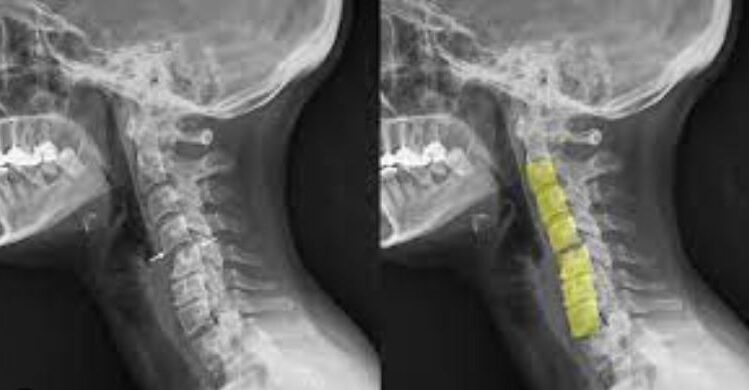

El diagnóstico de un latigazo cervical se basa en una evaluación clínica completa, que incluye un análisis detallado de los síntomas, el historial médico y, en algunos casos, pruebas complementarias. Algunas de las pruebas más comunes para confirmar el latigazo cervical son:

Radiografías: Para ver el estado de las vértebras cervicales y realizar un diagnóstico, descartando fracturas o daños en los huesos de la columna cervical.

Resonancia magnética (RM): Para identificar lesiones en los tejidos blandos, como los ligamentos y los discos intervertebrales.

Tomografía computarizada (TC): En algunos casos, se puede utilizar una TC para obtener imágenes más detalladas de la columna cervical.